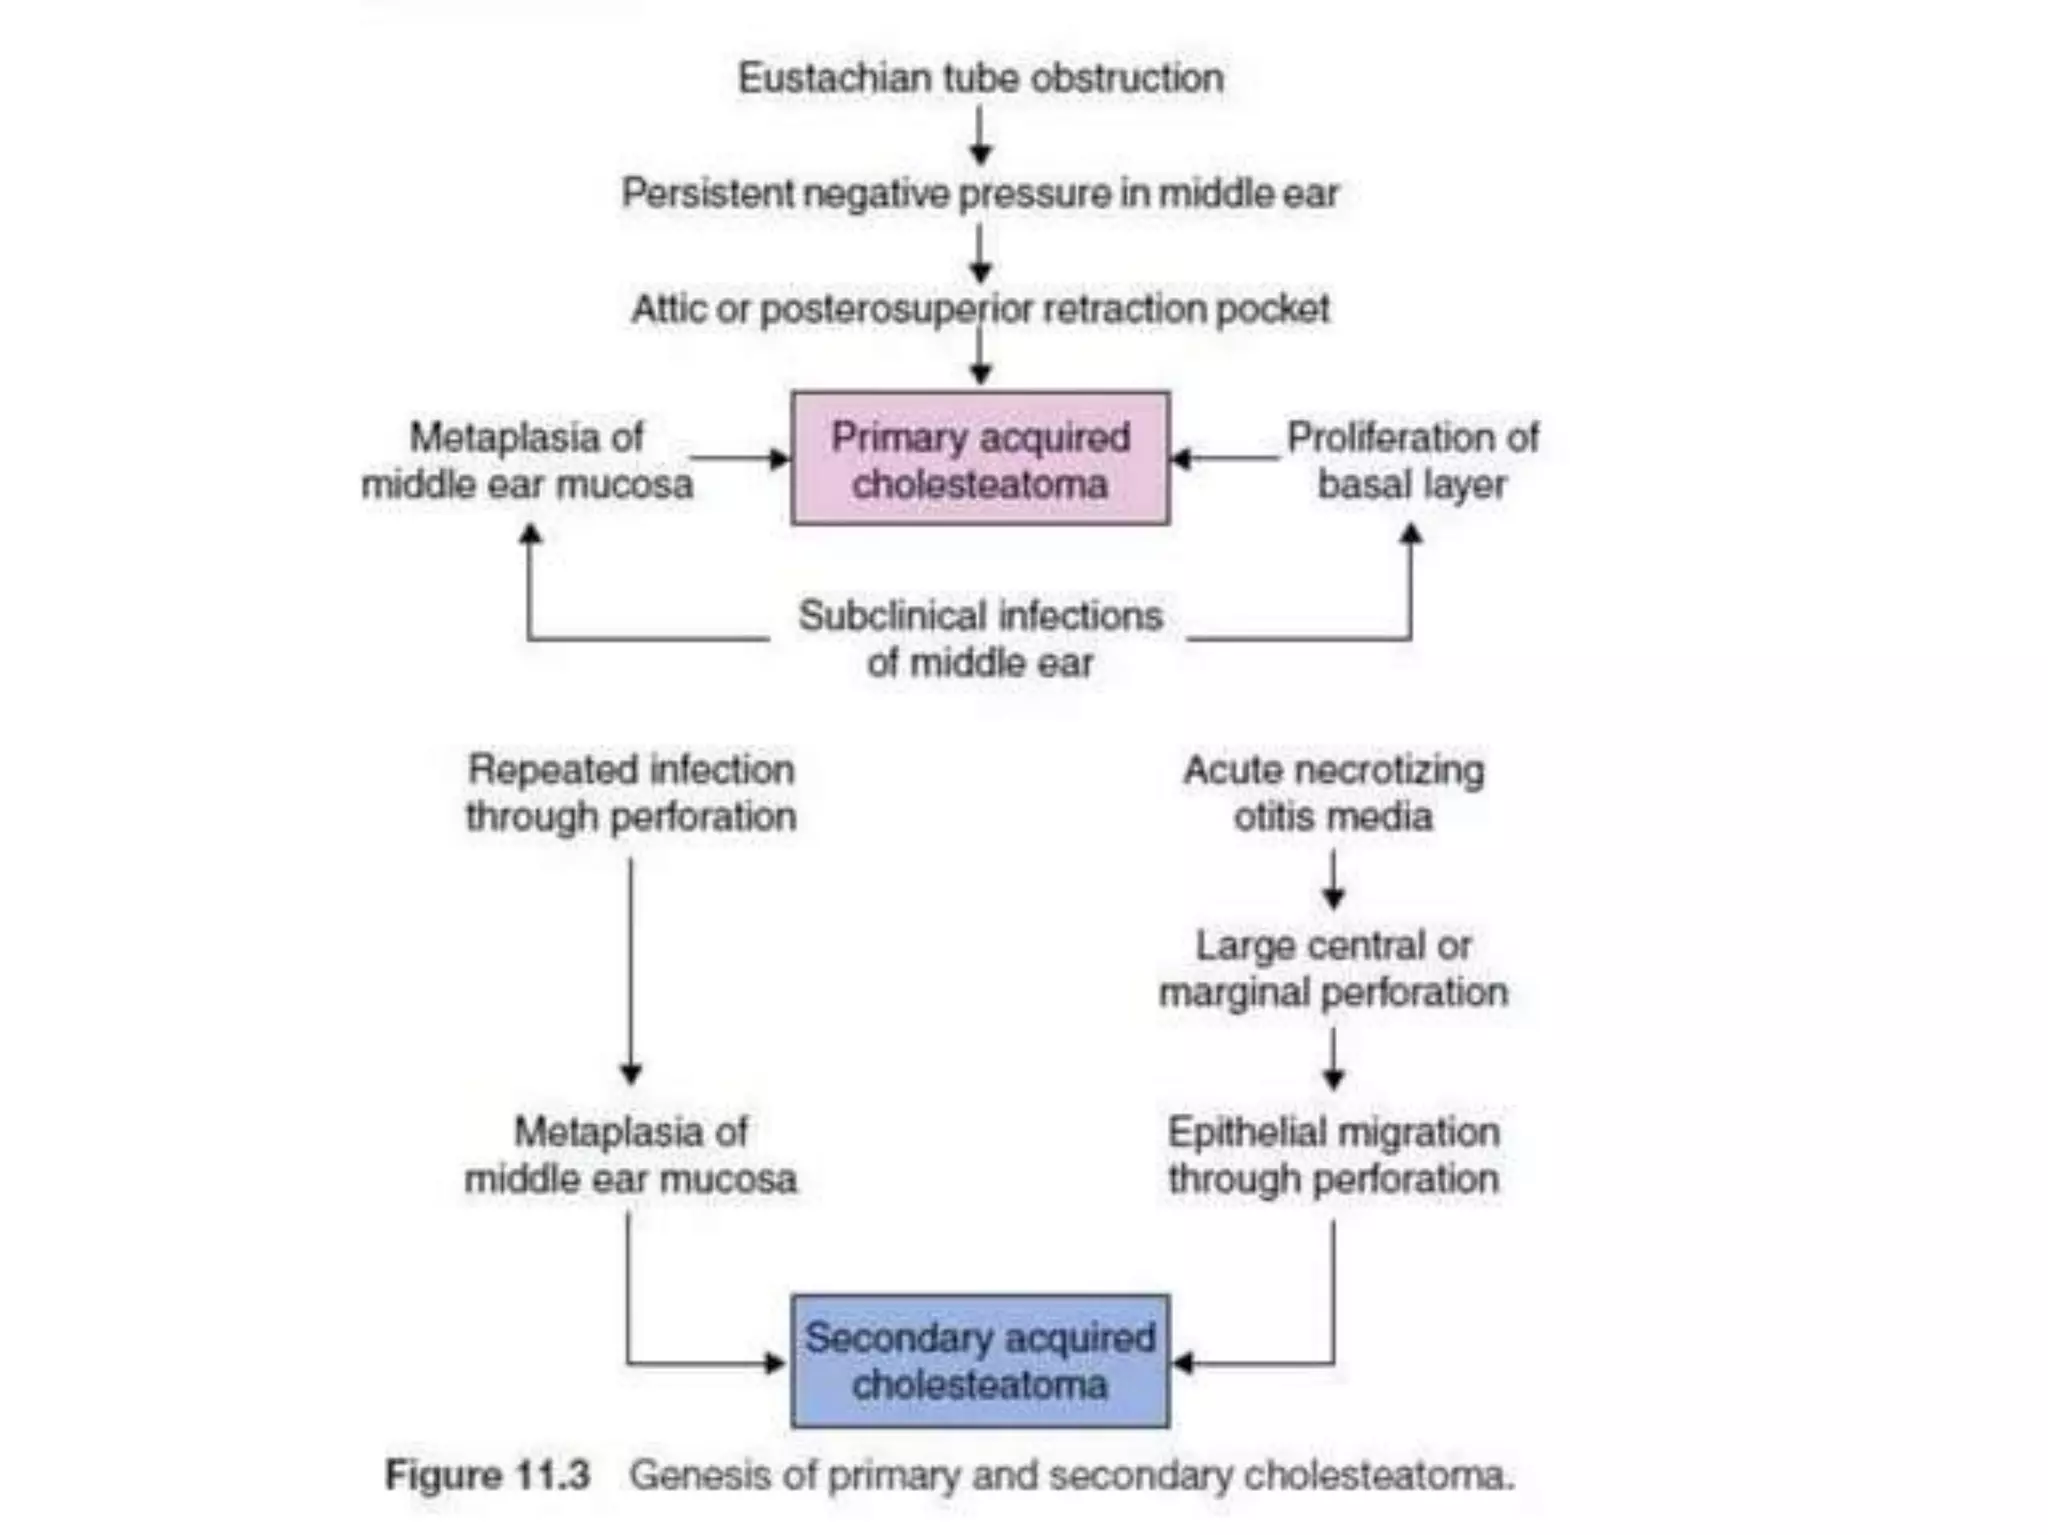

Chronic otitis media is a chronic inflammation of the middle ear and mastoid cavity that presents with recurrent ear discharge through a perforated eardrum. It has several subtypes depending on the state of the eardrum perforation and epithelium. It can be caused by prior acute otitis media, genetics, environment, eustachian tube issues, gastroesophageal reflux disease, craniofacial abnormalities, or immune deficiency.